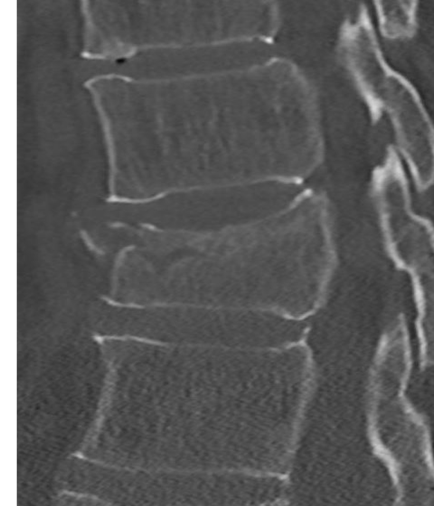

De wervelkolom (ruggengraat) ondersteunt het gewicht van het lichaam bij bewegingen en bij het aannemen van houdingen. Ook biedt het bescherming voor de zenuwbanen (het ruggen-merg). Het bestaat uit 33 of 34 wervels. Zeven halswervels, twaalf borstwervels, vijf lenden-wervels, vijf heiligbeenwervels en vier of vijf staartbeenwervels. Iedere wervel bestaat uit een wervellichaam en een wervelboog.

Stabiele of instabiele wervelbreuk

Bij een stabiele wervelbreuk is alleen het wervellichaam gebroken. Als een breuk stabiel is kan het wervellichaam niet verschuiven, waardoor het ruggenmerg niet beschadigd kan raken. Een operatie is dan niet nodig.

Bij een instabiele breuk is dit risico wel aanwezig en daarom is een stabiliserende operatie noodzakelijk. De revalidatie zal grotendeels overeenkomen met de revalidatie na een stabiele breuk zonder operatie.